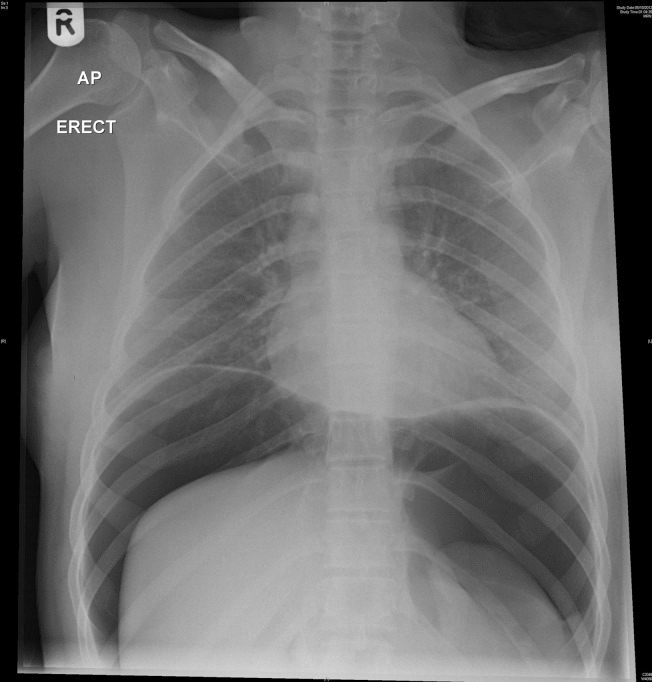

1 day

An 18-year-old female presents to the emergency department with abdominal pain and shortness of breath after drinking a fancy cocktail. Her x-ray is below. What do you think is going on?